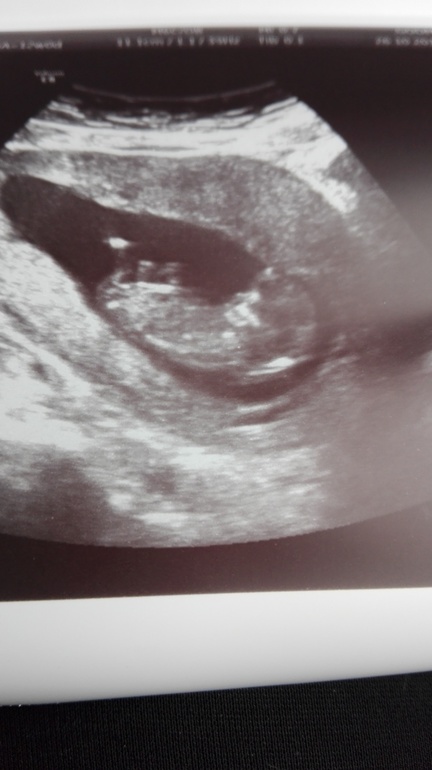

Узи в 12 недель)))Все хорошо)))

Поздравляю! Я по снимку даже не могу предположить пол(((сама делала неделю назад скрининг и тоже не сказали,а я и не спрашивала..врач все рассмотрел..но про пол ни слова..а у вас есть снимок первого сыночка?сравнить если..

Поздравляю!!! По снимку точно мальчик.

Спасибо большое) Мне как-то в душе тоже кажется, что мальчик) По снимкам я не сильна) А врача спросила, можем ли мы хотя бы предложить? А она: " Можете предпологать - мальчик или девочка)" на этом разговор был благополучно закрыт)